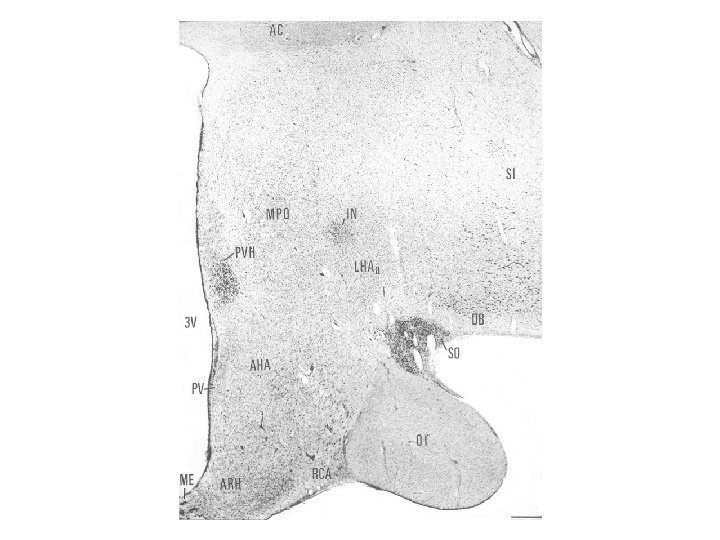

Gömöri’s staining

Hypothalamo-hypophysis rendszer Két részből, a nagysejtes hypothalamo-neurohypophysealis és a kissejtes tubero-infundibuláris rendszerből tevődik össze. A nagysejtes supraopticus és paraventriculáris neuronok vasopressint és oxytocint termelnek, axonjaik jelentős része (a supraopticus esetében az összes) a neurohypophysisben végződnek, ami quasi raktára a vasopressinnek és az oxytocinnak. A tubero -infundibuláris neuronok a hypophysis elülső részében levő endokrin sejtek neurohormonjaik termelésének szabályozását és felszabadításukat (release -t) végzik. A hypothalamus különböző részeiben termelődő neurohormonok nem közvetlen úton, hanem neurohumorális transzport révén jutnak a hypophysisbe: axonjaik az eminentia mediana vér-agy gát-mentes kapillárisaiba ürítik szállított termékeiket, melyek a portális erek révén jutnak a hypophysis elülső lebenyébe.

Hypothalamus szerepe a só- és vízháztartás szabályozásában A vasopressin a magnocellularis paraventricularis és supraopticus magokban termelődik. A vasopressint korábban antidiureticus hormonként (ADH) írták le, és ez az elnevezés ma is használatos a klinikumban. A vasopressin szintézisében és a neurohypophysisbe juttatásában, illetve az onnan történő felszabadításában két másik hormon az angiotensin II, és atrialis natriureticus hormon visz szerepet. Az előző a vesében termelődő renin-angiotensin rendszer aktív tagja, mely a vér-agy-gát-mentes subfornicalis szerven keresztül jut be az agyba, míg az utóbbit a preopticus area neuronjai termelik.

Nucleus paraventricularis hypothalami A hypothalamus egyik legjelentősebb magja, magno- és parvocellularis részre osztható. A magnocelluláris neuroszekretoros sejtek vasopressint és oxytocint termelnek, axonjaik a tractus hypothalamo-hypophysealis egy részét alkotják, és a hypothalamus hátulsó lebenyében végződnek. A parvocelluláris neuroszekretoros idegsejtek több peptiderg neurohormont (corticotropin-releasing hormon – CRH, thyrotropin-releasing hormon – TRH, vasopressin) és neuromodulátort (neuropeptidet) termelnek. A parvocellularis neuronok egy része az eminentia mediana portális erei révén juttatja el termékét a hypophysis elülső lebenyébe, másik részük a nyúltvelőbe és a gerincvelőbe projíciál. A CRH-termelő idegsejtek révén a paraventriculáris magot a stresszválasz központi részének, a „hypothalamohypophysis-mellékvesekéreg szabályozó rendszer” („HPA axis”) kiinduló pontjának tekintik.